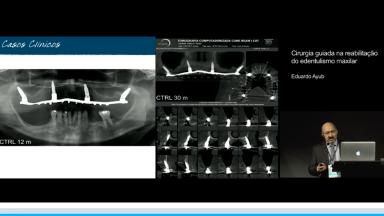

Cirurgia guiada na reabilitação do edentulismo maxilar

Esta conferência discute a cirurgia guiada assistida por computador, em maxila totalmente edêntula. As guias cirúrgicas são desenhadas e impressas a partir do planejamento cirúrgico em ambiente virtual, com a utilização de programas de software de planejamento que associam exames de tomografia computadorizada (CT) da anatomia óssea do paciente ao planejamento protético. Apresenta evidências científicas sobre a vantagens clinícas e acuracidade na transferência do posicionamento do implante guiado em comparação com a instalação de implantes a mão livre. Concluindo que, por meio da sistematização do planejamento, junto a procedimentos cirúrgicos guiados, é possível otimizar a cirurgia, minimizar complicações e oferecer mais conforto para o paciente.